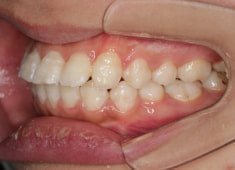

治療後(1年12ヶ月後)